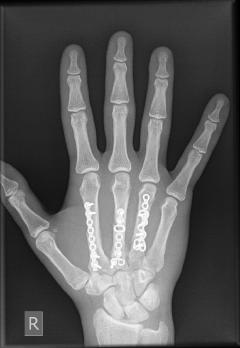

Deformities - Injuries

Fractures of metacarpals and digits of the hand

Fractures of the metacarpals and digits are common in laborers and athletes and can be part of a serious injury that includes tendons, nerves, vessels. The majority are treated surgically with the use of small implants (wires, mini screws and plates). In some cases the implants need to be removed after fracture healing.

These injuries are day-cases. They require a meticulous and strictly followed postoperative program conducted by a properly trained physiotherapist under the surgeon’s supervision.